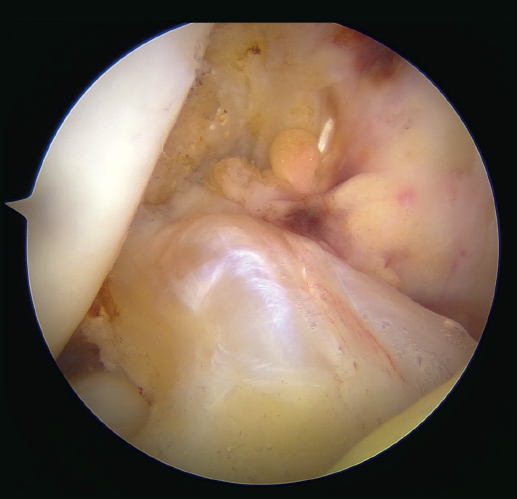

Once a good view of the central compartment is obtained, the area of the femoral footprint of the ACL is prepared to leave exposed bone, and microperforations are made in the medial wall of the lateral condyle to leave a bleeding bed to favor healing of the ligament (Figure 3). These microperforations can be made using specific instruments or with the implant punch. The advantage of using the punch is that the implant insertion site can be prepared at the same time, and only one instrument is used for the entire process (Figure 4). This step can be done after the suture has been prepared in the ligament, although doing it beforehand avoids the threads from standing in the way. The ideal point for fixation is just anterior to the native ACL footprint, although if the tear is partial or corresponds to Sherman I, it can be taken to the anatomical footprint without difficulty.

The anteromedial and posterolateral fascicles of the ACL are then identified for suturing separately. Using a suture passer, a closed loop suture is passed through the anteromedial fascicle at its most distal zone, and the loopless extremity is carried alternately (medial to lateral, lateral to medial and so on) to the most proximal zone, usually involving 3 or 4 passes of the suture. The thread may knot on itself during suturing if we are not attentive to it on entry and exit. To solve this problem, we simply undo the knot with retrieval forceps and repeat the step if necessary.

On completion, the thread is retrieved through the accessory anteromedial portal. The process is then repeated, this time with the posterolateral fascicle. To prevent the first thread from breaking with passage of the second thread, it must be ensured that entry and exit in the ligament are very posterior and ideally somewhat proximal to those used for the anteromedial fascicle. Once having reached the most proximal zone after 3 or 4 passes, retrieval is carried out in the same way through the accessory anteromedial portal.

Outside the knee, the threads are loaded into a knotless anchor implant with a tape that will act as anterior reinforcement of the ACL when attached to the tibia. Once the implant has been loaded, it is inserted into the previously prepared site. This step is facilitated when viewing is made from the anteromedial portal, as it affords a better perspective of the zone (Figure 5). Once the implant has been inserted, the suture threads are cut at the level of the condylar wall.